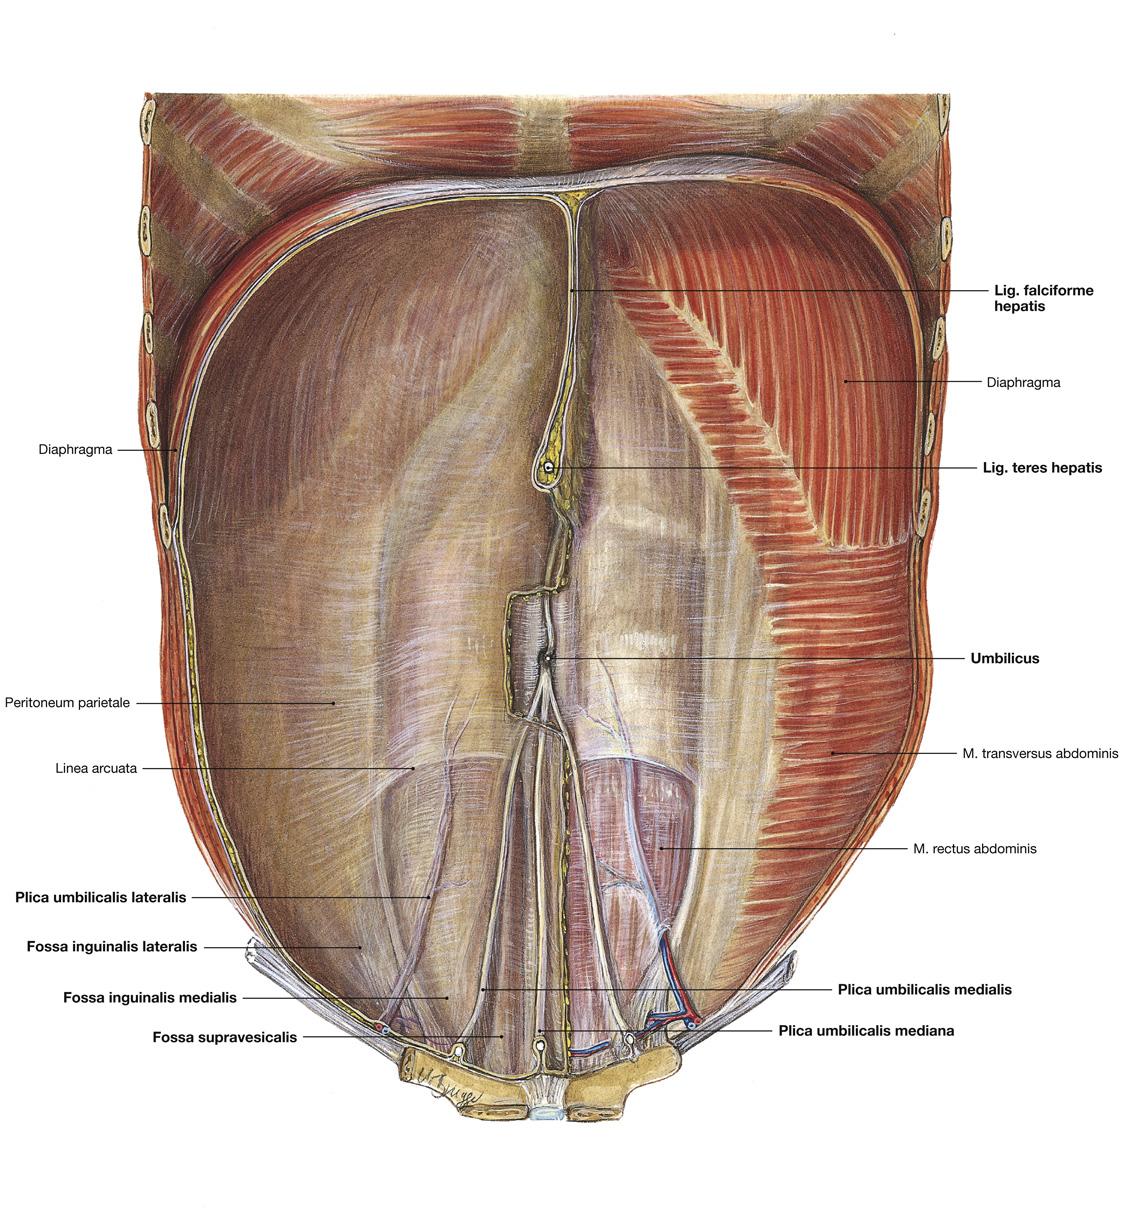

Fig 3.29a: Details

A binnenkant buikwand

navel os pubis blaas lig inguinale m iliopsoas lig lacunare a femoralis v femoralis -

plica umbilicalis medialis

plica umbilicalis medianum (= geoblitereerde urachus) -

plica umbilicalis lateralis

-

inwendige liesopening

-

fossa inguinalis medialis

-

fossa inguinalis lateralis